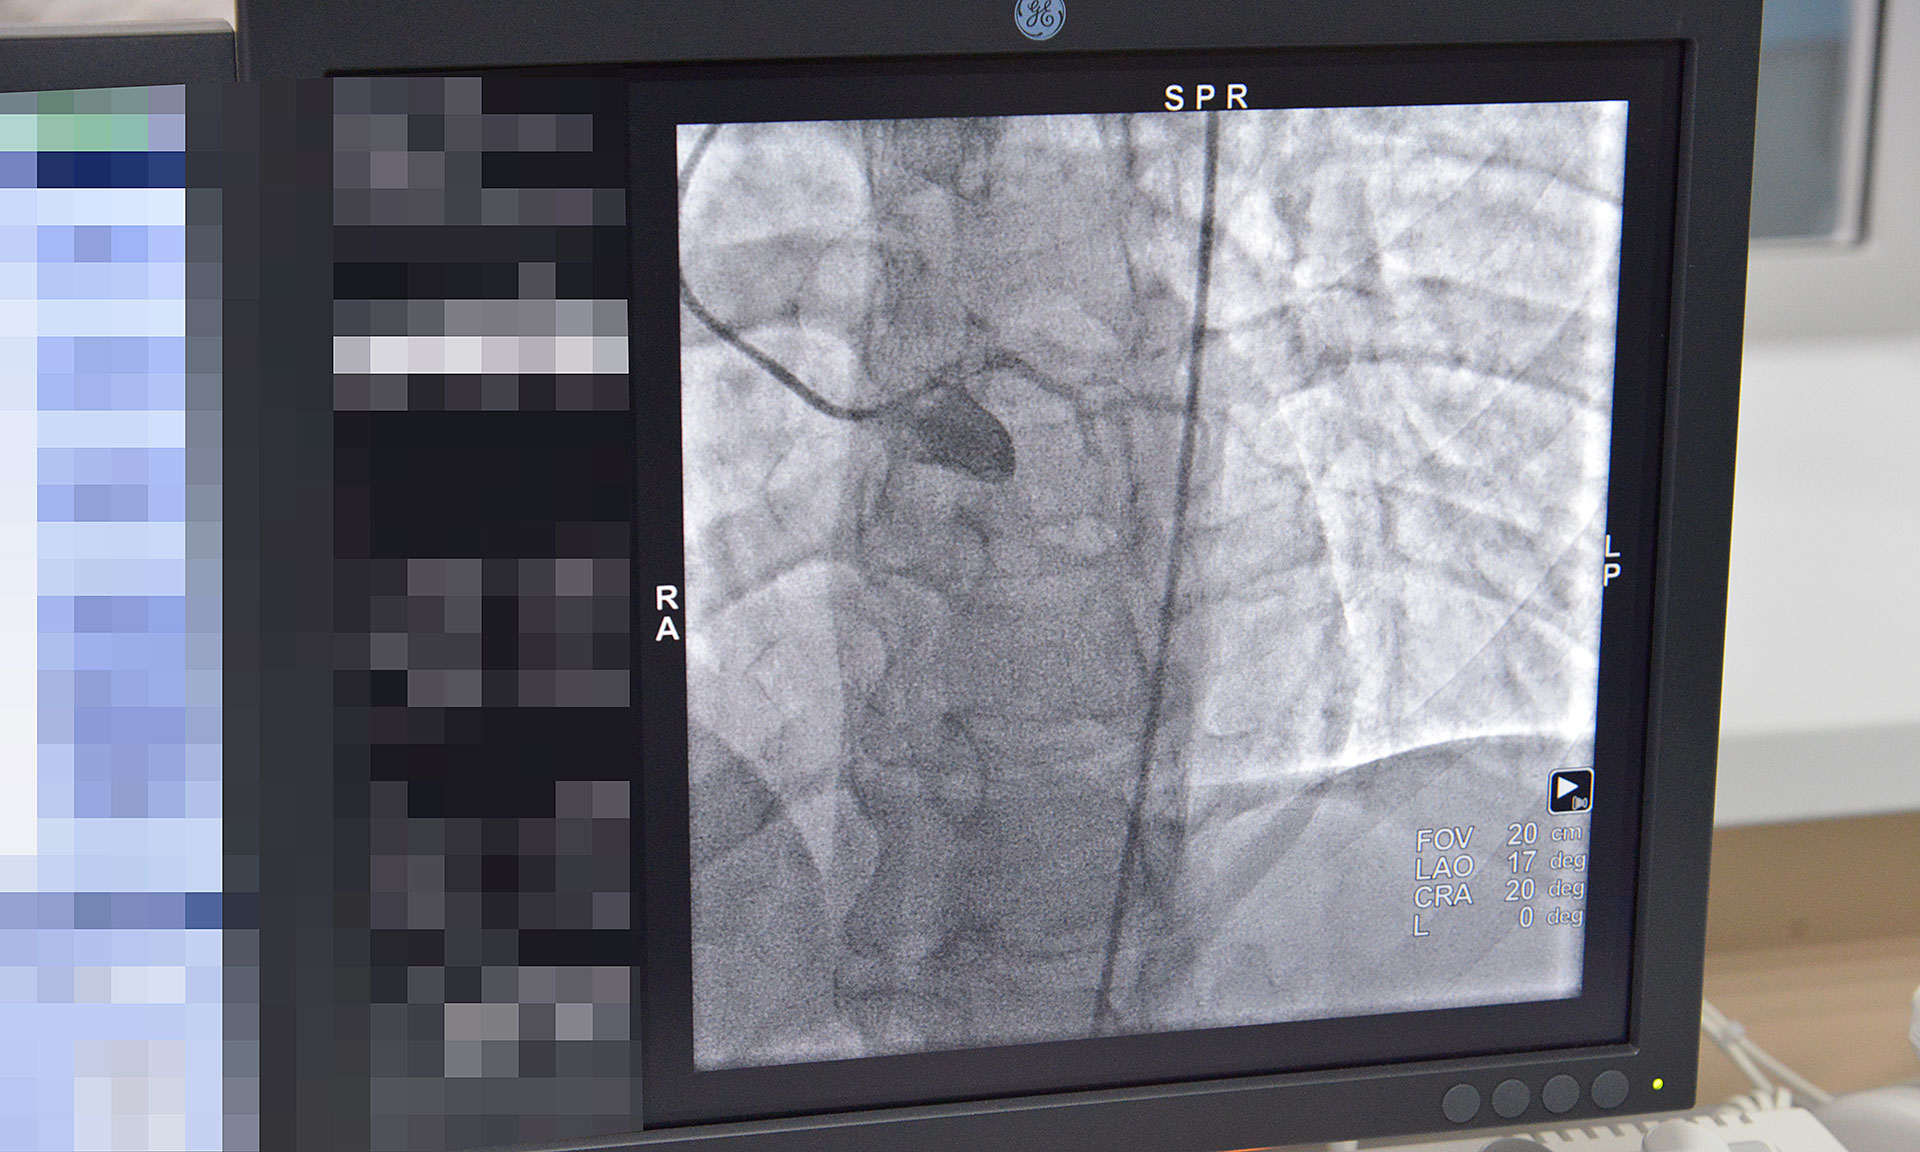

13 марта Губернатор Брянской области Александр Богомаз посетил отделение рентгенохирургических методов диагностики и лечения второго регионального центра для лечения больных с сердечно-сосудистой патологией Брянской городской больницы № 1.

Главный врач Брянской городской больницы № 1 Константин Воронцов сообщил, что с февраля 2018 года в ГАУЗ «Брянская городская больница № 1» функционирует новое структурное отделение рентгенохирургических методов диагностики и лечения. Данное отделение открыто благодаря приобретению дорогостоящего оборудования -ангиографической установки «Инова» за счет денежных средств, выделенных областным бюджетом в сумме 37 млн. рублей. Это позволит открыть второй региональный центр для лечения больных с сердечно-сосудистой патологией, применяя высокотехнологические методы лечения, а именно: стентирование коронарных сосудов, сосудов нижних конечностей; оперативное лечение сосудистой патологии головного мозга.

В настоящее время в отделении проводится коронарография пациентам с сердечно-сосудистой патологией. В дальнейшем, при получении лицензии на проведение высокотехнологической медицинской помощи, будет проводиться стентирование сосудов.